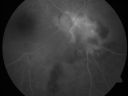

63-year-old woman has serpiginous choroiditis (date - March 2011). She has only had disease in the left eye. She had a steroid implant with your group in August of 2006. I injected the eye with Kenalog in January of 2007 and then she had another Kenalog injection in June of 2007. The right eye has not been previously involved, and then she noticed new onset floaters in the right eye for the last two weeks. Her vision in the right eye is hazy because of that. She is on Cosopt and Combigan in the left eye because of her steroid responsive glaucoma.

VISUAL ACUITY: Vision OD is 20/25, OS is 20/50. IOP: OD 13, OS 11. The right eye has 2+ nuclear sclerosis. There are 2+ anterior vitreous cells. The left eye has a posterior chamber intraocular lens in good position. The eye is quiet.

OD: Vertical C/D ratio is 0.3. There are 2+ vitreous cells. There is a new area of chorioretinitis inferonasal to the optic nerve, which is white and extends about 2-3 disc diameters off the nerve.

OS: Vertical C/D ratio is 0.8. There is extensive chorioretinal scarring but there is no active inflammation.

1. ACTIVE SERPIGINOUS CHOROIDITIS – RIGHT AND GOOD EYE

2. PREVIOUS MACULAR SCARRING FROM SERPIGINOUS CHOROIDITIS – LEFT EYE